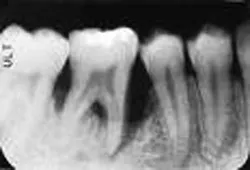

Sonoporation refers to transdermal drug delivery using ultrasonics. When something vibrates ultrasonically in a liquid, the pressure oscillations created can raise the temperature of small regions of the liquid to the boiling point. This creates a stream of microscopic cavitation bubbles flowing out from the vibrating source. When the bubbles collapse, a jet of fluid rushes through the center of the bubble with incredible pressure (see Figure 3). You could think of this jet as a microscopic battering ram or as an injection.